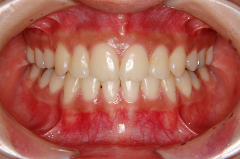

装置装着前

装置装着後